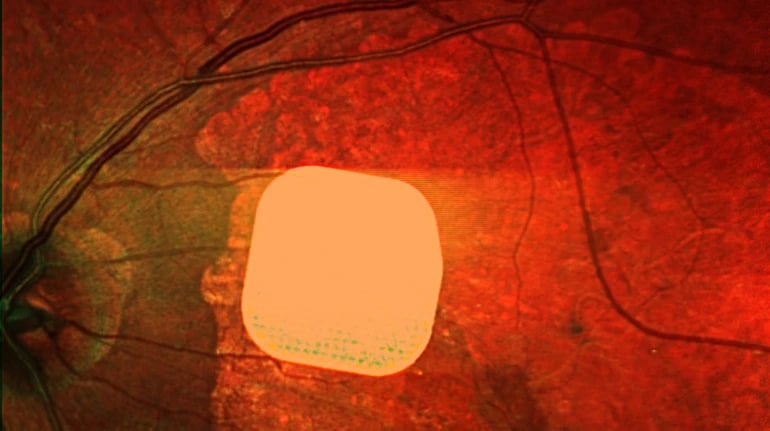

Британські лікарі успішно випробували новий електронний імплант Prima, який допомагає пацієнтам із макулодистрофією, що призводить до втрати зору після 50 років, частково відновити зір. Мікрочип розміром 2×2 міліметри встановлюється під сітківку ока і з’єднується з камерою та комп’ютером у спеціальних окулярах. Після операції 84% пацієнтів знову могли розрізняти літери, цифри та слова. Лікарі вважають, що ця технологія відкриває нові можливості для людей зі втратою зору, допомагаючи покращити їхню якість життя.

Британські лікарі частково повернули зір пацієнтам за допомогою мікрочипа